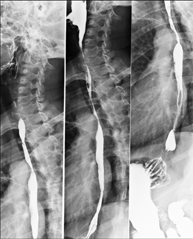

- Oesophagogram

Diagnostic test to obtain moving radiological images of the oesophagus, using X-rays (fluoroscopy) and an opaque barium contrast agent administered orally.

- EGDT (Oesophageal-gastro-duodenal transit)

Diagnostic test to obtain moving radiological images of the oesophagus, stomach and duodenum using X-rays (fluoroscopy) and an opaque barium contrast agent administered orally.

- Intestinal transit

Diagnostic test to obtain moving radiological images of the oesophagus, stomach, duodenum and small intestine using X-rays (fluoroscopy) and an opaque barium contrast agent administered orally.